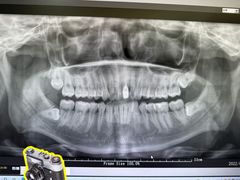

• 牙博士口腔品牌连锁(杨浦店)

• -牙博士口腔品牌连锁(杨浦店)

**Ray**_2998 | 22-09-25